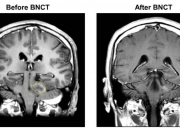

液体胶水成分有望提升硼中子俘获疗法治癌的适用范围

图片来源于网络,如有侵权,请联系删除 新华社东京12月13日电(记者钱铮)日本研究人员日前宣布,他们发现液体胶水的一种成分,在与一种化合物结合后能大大提升硼中子俘获疗法治疗癌症的适用范围和疗效,并在动物实验中取得了接近根治癌症的效果。 硼中子俘获疗法是几十年前提出的一种创新的放射治疗方法。该方法首先为患者注射含硼药物,这类药物和癌细胞有很强的亲和力,并很快聚集在肿瘤细胞内,而很少在正常组织中聚集。然后对患者的肿瘤部位进行热中子照射。当热中子被肿瘤细胞中的硼-10同位素俘获...